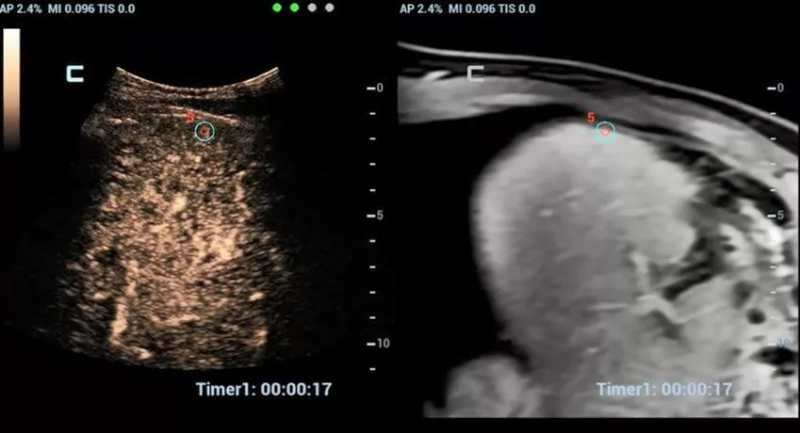

To settle this problem, the iCompare feature of DC-80 with X-Insight came into being. It allows ultrasound users to compare real-time ultrasound imaging to the past DICOM CT/MRI/Mammography/X-Ray/Ultrasound images without external workstation which is extremely helpful to evaluate and follow up the progression of disease as well as to monitor treatment effect. For ultrasound users who are suffered from such challenge, the iCompare solution is indeed a savior.

iCompare of CT and US